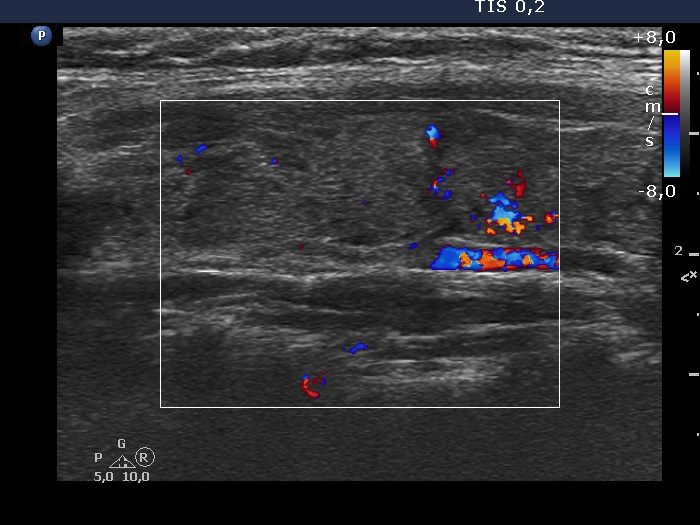

Discrete lesion or nodule in Hashimoto's thyroiditis - case 27 (1029) (ultrasonographic picture 7)

Left lobe, longitudinal scan, color Doppler mode. The vascularization is not specific.